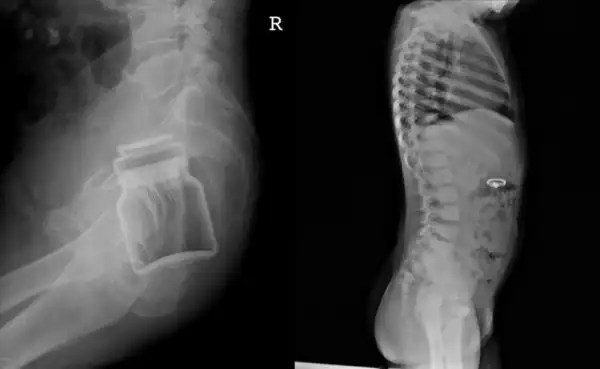

Проход держать закрытым